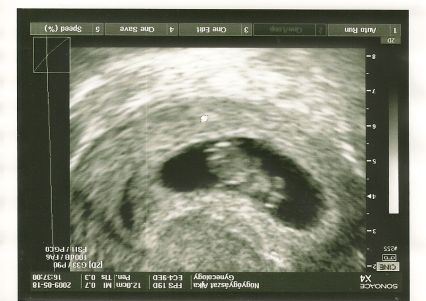

Tulipános! De jó a kép! Az elsőn pont elölről látni, nagyon édes!